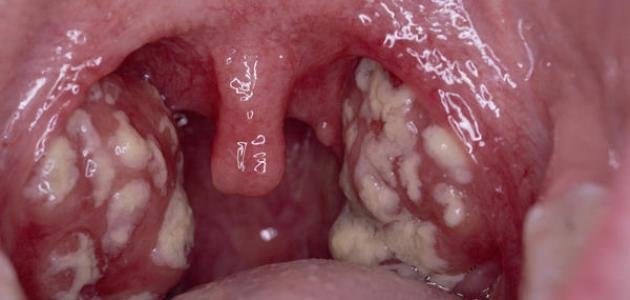

4. ملاحظة احمرار اللوزتين، والشعور بآلام بالحلق.

6. ملاحظة وجود أغشية بيضاء أو صفراء اللون على اللوزتين.